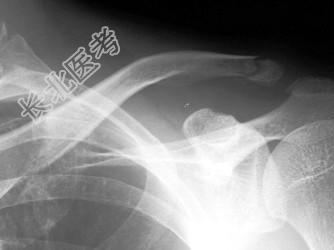

- 单项选择题男,25岁, 外伤后摄片,结合图像, 最可能的诊断是 ( )

A、肋骨骨折

B、锁骨骨折

C、原发性气胸

D、肋骨骨折伴气胸

E、锁骨骨折伴气胸